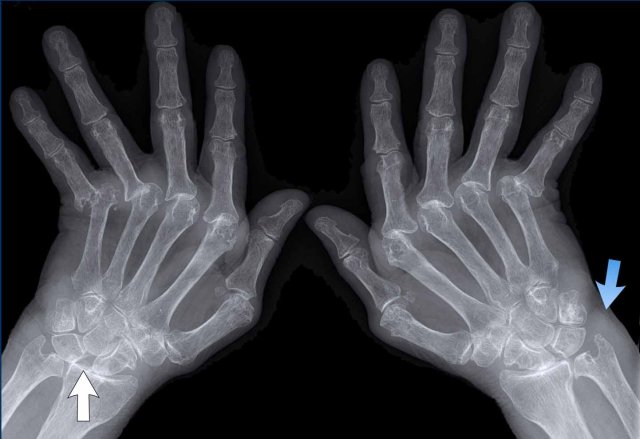

Rheumatoid arthritis in the feet Rheumatoid arthritis in the feet

In this case of rheumatoid arthritis there are marginal erosions adjacent to almost all MTP joints (arrowheads).

The 5th MTP joint is most frequently involved in  rheumatoid arthritis.

When erosions are as severe as in this case, it can look like pencil-in-cup deformity (white arrow) as is frequently seen in psoriatic arthritis.

However, the primarily affected MTP joints distribution and less affected interphalangeal joints is the clue that this is a case of rheumatoid arthritis.